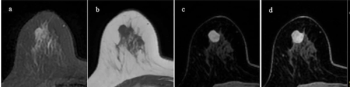

The absence of ipsilateral breast hypervascularity is three times more likely to be associated with false-negative findings on breast MRI and non-mass enhancement lesions have a 4.5-fold likelihood of being linked to false-positive results, according to new research.